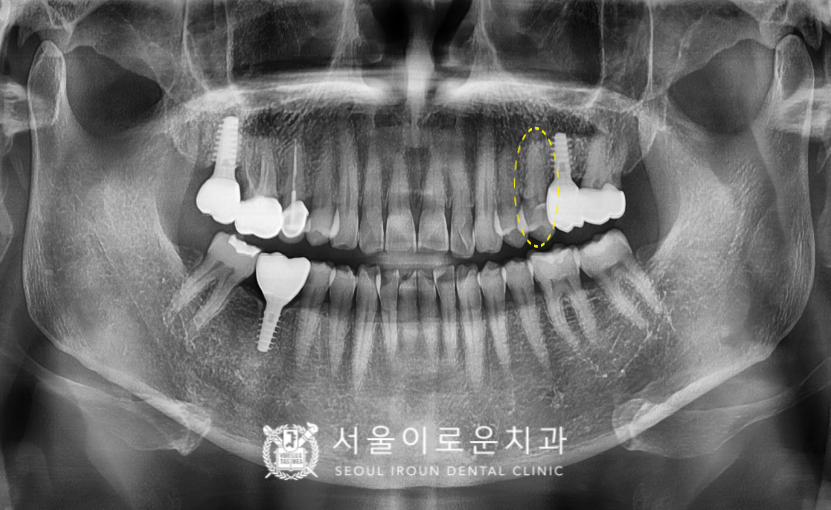

파노라마 사진상으로는

파절 양상이 확연하게 보이진 않지만

구강 내 체크를 해보았더니

위턱 왼쪽 두 번째 작은 어금니가(#25)

뿌리 부분까지 둘로 쪼개져 있는 것을

확인할 수 있었습니다.

크라운 보철물 치료가 마무리 된 모습의

파노라마 사진과 구강 내 사진입니다.